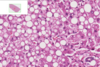

Which is normal and which abnormal liver? What type of reversible cell injury? How can you tell?

Left is abnormal, right is normal

Hydropic change in hepatocytes

Indicated by swollen, clear cytoplasm